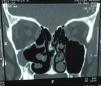

En las radiografías simples se apreciaba opacidad, así como medialización del maxilar izquierdo y descenso aparente del piso de la órbita, por lo que se solicitó, como estudio de imagen complementario, una tomografía computada de nariz y SPN en la ventana ósea (fig. 3).

En la tomografía se puede apreciar la disminución del tamaño del seno maxilar, ocupado en su totalidad por una isodensidad de tejidos blandos, con engrosamiento de la pared lateral del mismo, discreta elevación de la fosa canina, así como un descenso evidente del piso de la órbita, con desplazamiento lateral del canal infraorbitario. Destaca una opacificación de igual manera por una isodensidad de tejidos blandos en la etmoides anterior, lo que habla de un involucramiento patológico de otros senos paranasales, además del directamente afectado. El tejido blando orbitario presenta características normales.